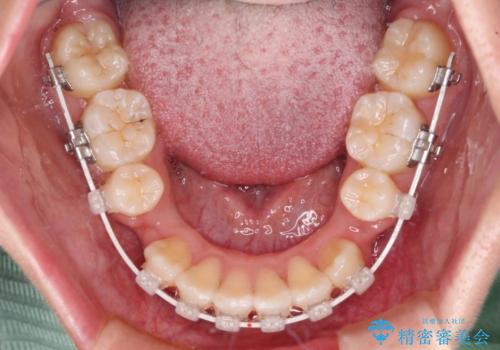

- 審美装置

- 2年3ヶ月

- 10-30回